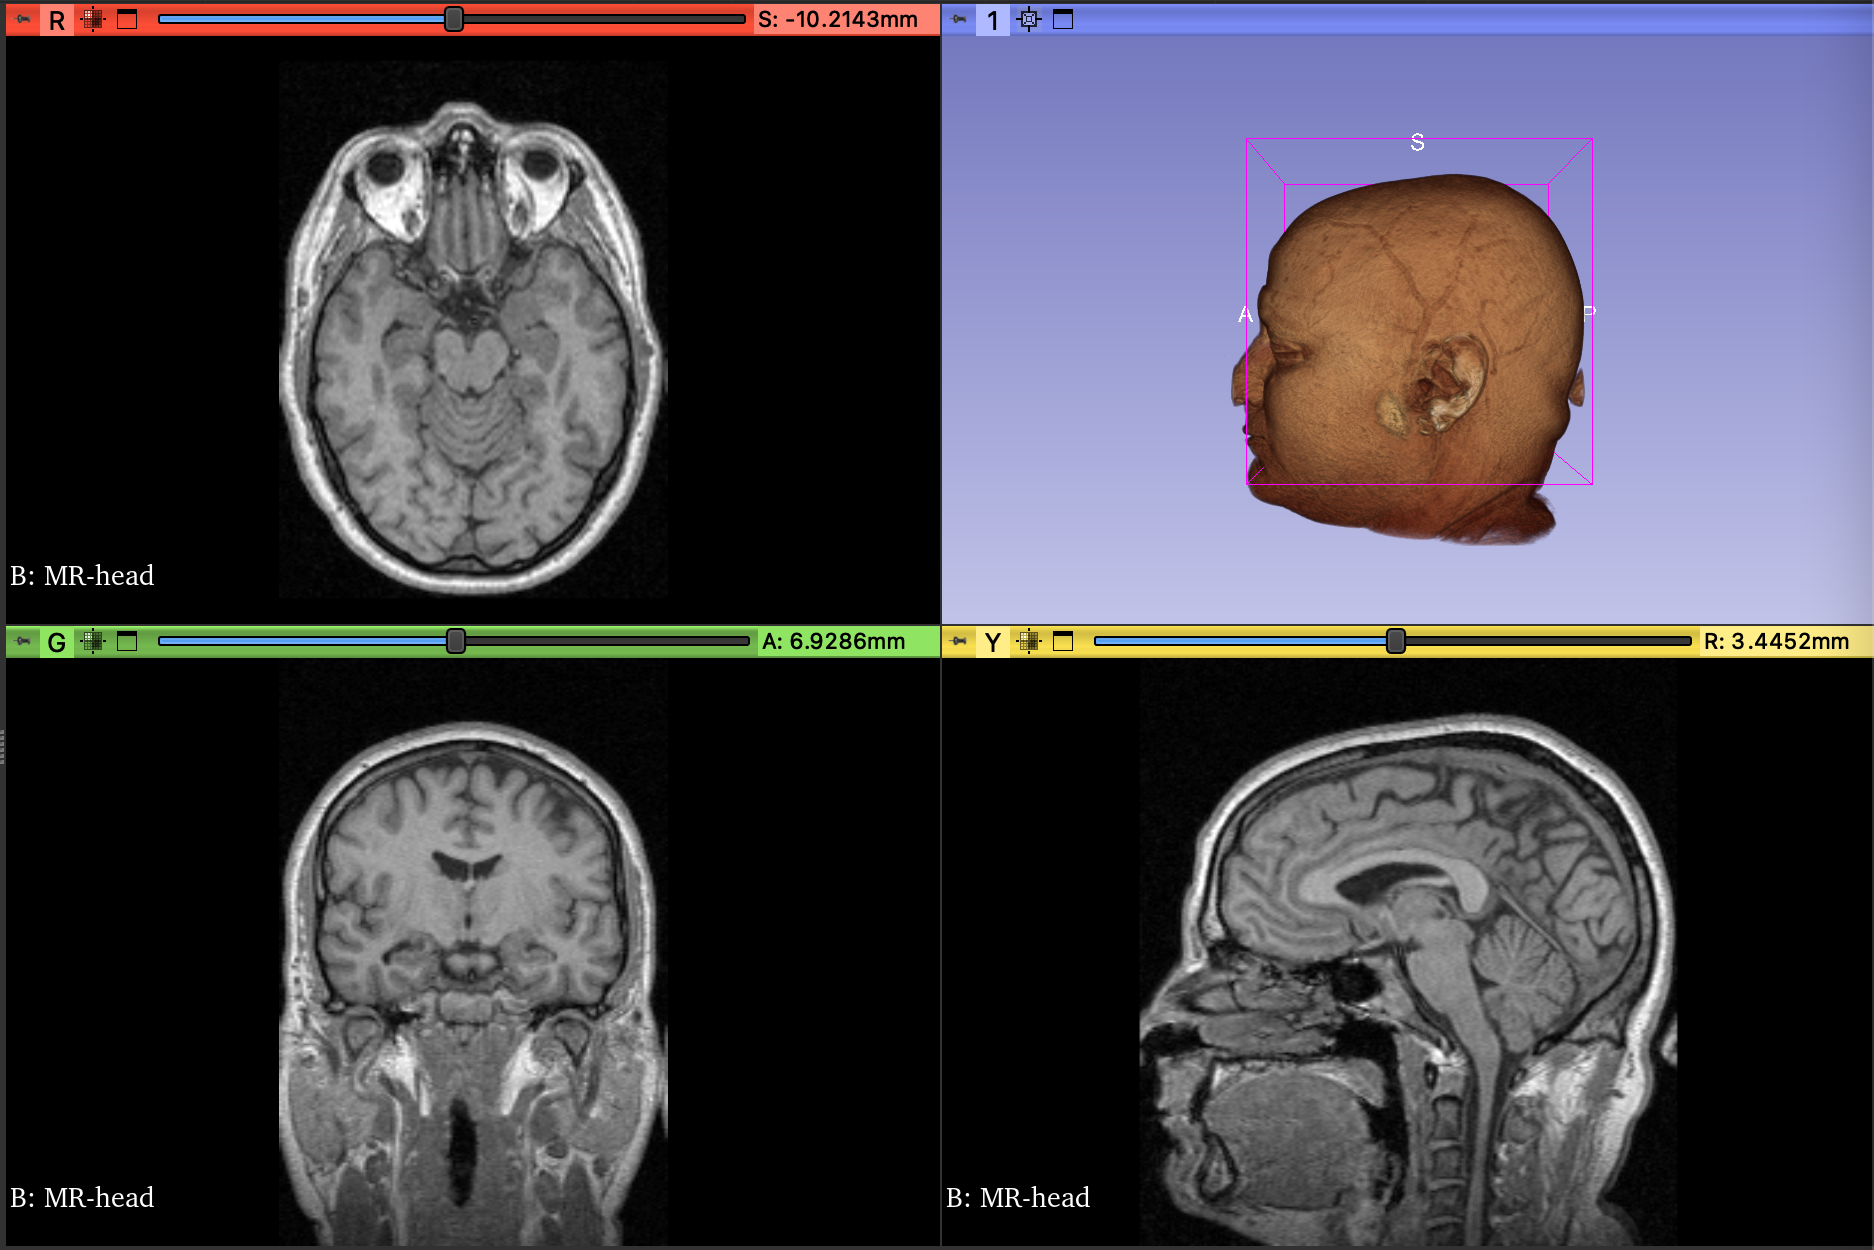

Fig. 11 shows the result of the QHED algorithm applied to a 3D model. This result was gained using an ideal simulator at the image decomposition level with a D-NISQ simulation. The model size is 256x256x130 voxels which is then buffered and decomposed into 5 qubit (32 voxel) subdomains to be distributed. The output of each subdomain is collected, post-processed, and reassembled. Threshold values are applied for visual purposes with the output shown in Fig. 11.

Refer to caption

Figure 11: The 3D MRI model, sourced from the National Cancer Institute (top), is processed and passed through the distributed QHEDM algorithm using an ideal quantum simulator (bottom). The images are generated using the image-level decomposition methodology on an HPC cluster.